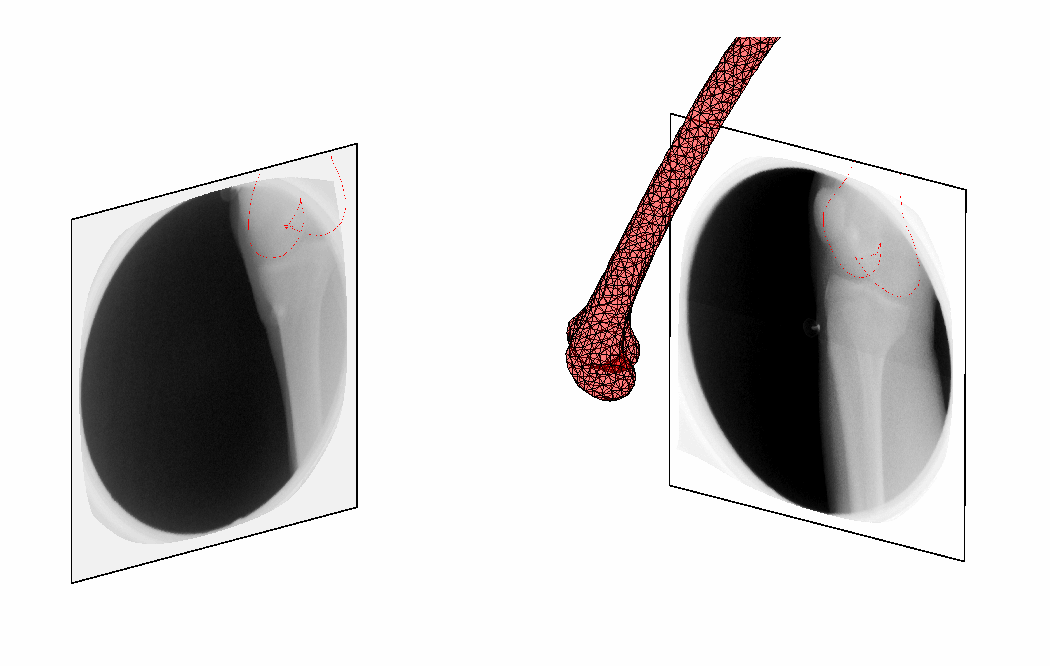

In current clinical practice, medical imaging plays a key role in diagnosis, therapy planning and therapy monitoring. Some of these modalities, such as CT, MRI, and 3D ultrasound, provide high resolution volumetric anatomical information, and more recently, 3D imaging in time. In certain practical situations, however, limitations with respect to imaging time, space, radiation dose, or ergonomics make it impossible to acquire such rich data. In such cases, imaging may be performed that is of lower dimensionality than the desired information, or is sparse in at least one of the dimensions. This type of sparse imaging is investigated in this thesis. Sparse imaging is typically employed in image guided interventions and surgeries, where high speed, high image resolution and an open acquisition setup are of major importance. The 3D position of the surgical instruments with respect to the 3D patient anatomy is then assessed through 2D imaging such as X-ray fluoroscopy or Ultra-soun. For similar reasons mono- and biplane X-ray fluoroscopy became the standard for kinematic analysis of joints, allowing the acquisition of a wide range of motions, such as running and jumping. In other situations, radiation dose and cost reduction play a mayor role in employing sparse imaging. Bone surface reconstruction from points pin-pointed during knee surgery e.g. has been investigated for replacing prior CT acquisition. Also, assessment of organ motion, such as cardiac or respiratory motion, can occur from temporally sparse CT images.